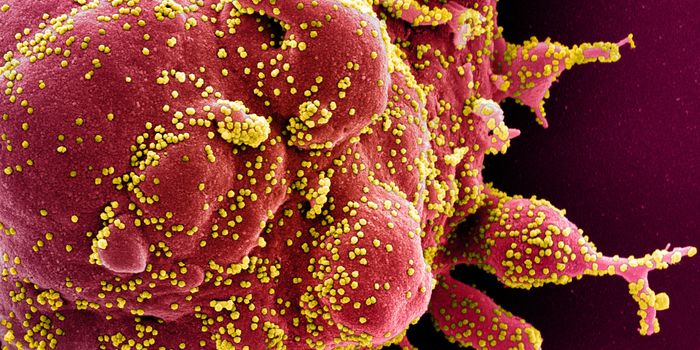

AUG 19, 2020Cell & Molecular BiologyAs the pandemic virus, SARS-CoV-2 continues to cause tens of thousands of new cases of COVID-19 every day in the United ...

APR 27, 2020MicrobiologyThe pandemic virus that causes COVID-19 has now infected nearly 3 million people, and killed over 200,000.

MAY 10, 2021MicrobiologyThe pandemic virus SARS-CoV-2 has changed the world in devastating ways, taking hundreds of thousands of lives & new var ...

MAR 03, 2020MicrobiologyThere have now been nine deaths in the United States, all in Washington state from COVID-19, the illness caused by the n ...

MAR 10, 2020MicrobiologyThe vast majority (97.5%) of people will develop symptoms of infection within 11.5 days of exposure to the virus.

NOV 01, 2020MicrobiologySARS-CoV-2, which causes COVID-19 has to get into cells to cause infection. It does so with a spike protein on its surfa ...